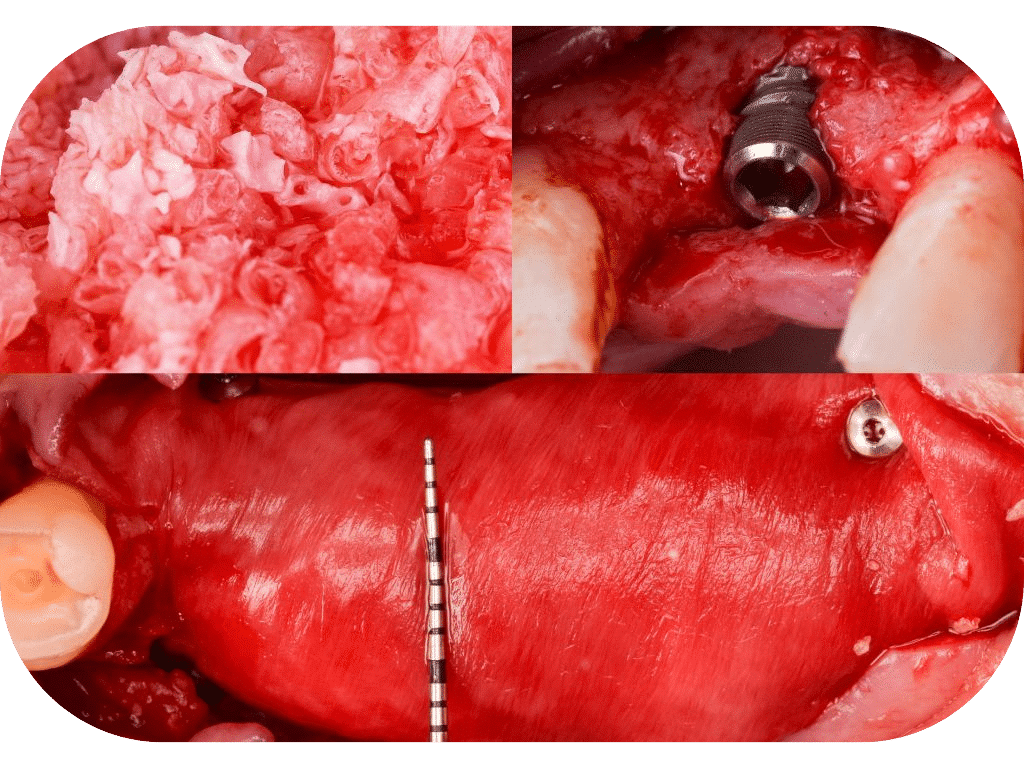

Overcoming Deficiencies with GBR & Sinus Techniques

Dive deep into the core principles of guided bone regeneration (GBR) and sinus lift techniques. Learn how to handle various osseous deficiencies and optimize implant placement success from our globally recognized Misch Educators. Emphasizing hands-on learning and interactive case-based discussions, the course enables dental professionals to improve their proficiency in handling challenging scenarios and complex anatomical structures. Upgrade your skills and case management abilities!

Hands-On Day 1: In this practical session, participants will gain experience placing implants in deficient sites, and performing simultaneous guided bone regeneration. This skill-focused session will provide participants with the knowledge and confidence to tackle challenging clinical cases in their own practices.

Hands-On Day 2: Attendees will immerse themselves in hands-on implant placement, learning the intricacies of simultaneous crestal sinus floor elevation to achieve optimal results. This clinical session will empower participants with the practical skills and knowledge to perform this advanced technique with confidence.